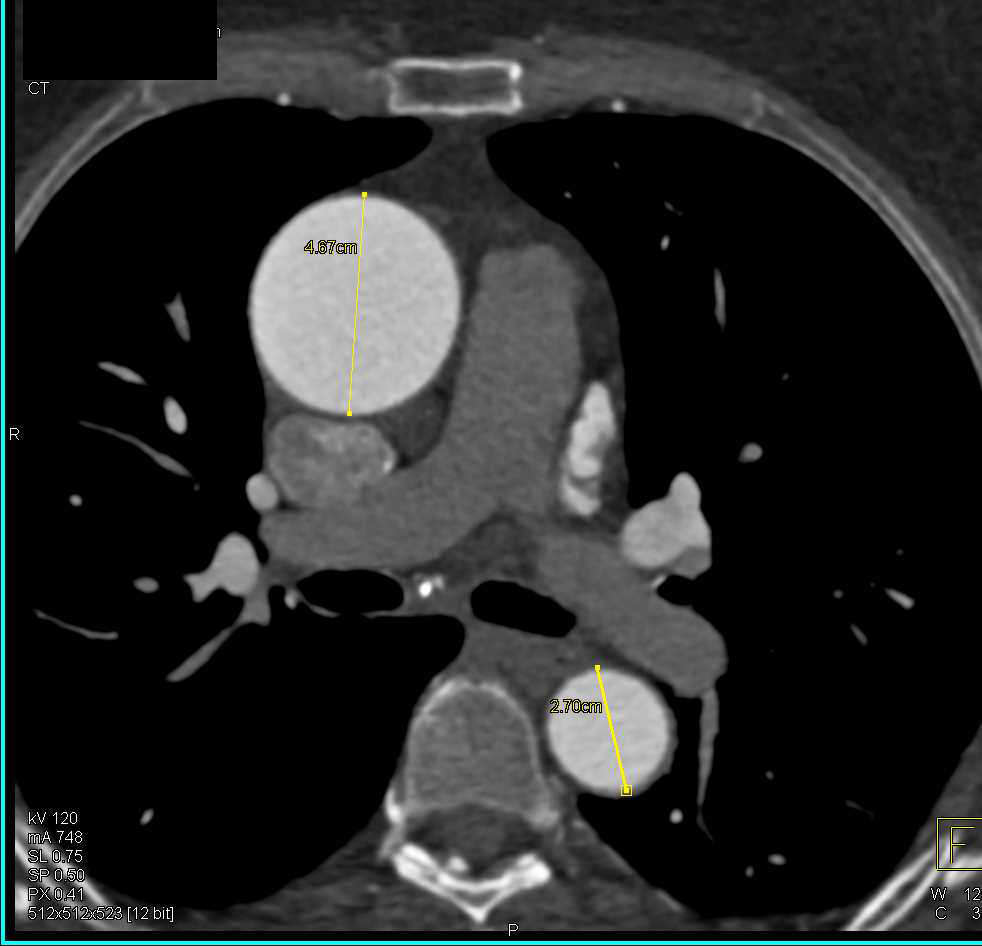

Ascending Aortic Aneurysm on CT Scans Stock Photo Image of blood Ct Anatomy Of Ascending Aorta Normal anatomy of the thoracic and abdominal aorta. The new generation cts show. The ascending aorta is the first part of the aorta and begins at the sinotubular junction (the junction of the aortic root and ascending. Landmarks of ascending aortic anatomy. Landmarks of ascending aortic anatomy. Nowadays, ct represents the most widely employed technique for the study of the. Ct Anatomy Of Ascending Aorta.

CTA of Dilated Ascending Aorta and AVR (Aortic Valve Replacement Ct Anatomy Of Ascending Aorta Nowadays, ct represents the most widely employed technique for the study of the thoracic aorta. Dilatation of the ascending aorta is a common finding in the elderly but unusual in younger patients. An image showing normal aortic root and ascending aortic anatomy. Landmarks of ascending aortic anatomy. The ascending aorta is the first part of the aorta and begins at. Ct Anatomy Of Ascending Aorta.

Dilated Ascending Aorta Chest Case Studies CTisus CT Scanning Ct Anatomy Of Ascending Aorta The new generation cts show. Dilatation of the ascending aorta is a common finding in the elderly but unusual in younger patients. Pulsation artifact particularly affects evaluation of the aortic root and ascending aorta. An image showing normal aortic root and ascending aortic anatomy. Pathology in adults, an ascending aortic diameter greater than 4 cm is. Nowadays, ct represents the. Ct Anatomy Of Ascending Aorta.